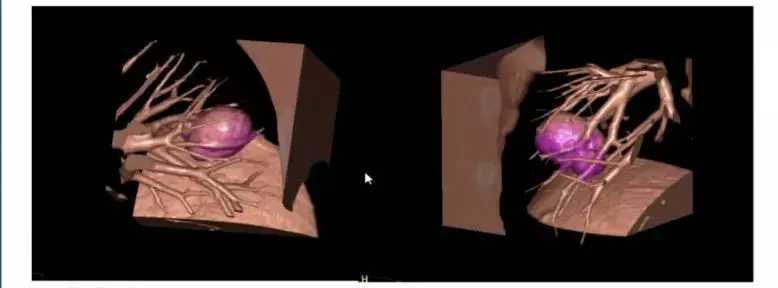

通常情况下,肺细胞瘤需与错构瘤进行鉴别诊断,在进行最大密度投影处理后,CT可见肺细胞瘤对周围血管有推移作用。经过影像后处理,可以通过进一步判断肺结节与附近病变和周围血管的关系进行诊断。

图5 图4-5 CT及处理后图像对比,可明确血管推移,进行诊断

图6 三维图像重建图像,此类情况需与肺内肉瘤和小细胞肺癌进行鉴别,嘱患者保持每3个月随访一次